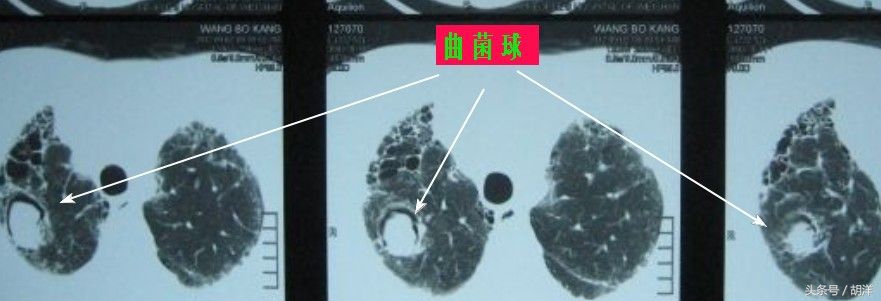

曲菌球形成

该类型主要发生于以前有过肺结核,支气管扩张,肺脓肿等疾病所致肺部空洞的患者,由于长期反复发作肺部普通细菌感染,患者常常因消耗而免疫力低下,曲霉菌容易乘虚而入,在空洞中寄生,而身体为了限制曲霉菌生长,会分泌白细胞,纤维素以及液体去消灭并包裹该菌,但身体的免疫力又不足以消灭真菌,慢慢的真菌、死去的白细胞、纤维素、身体分泌的液体长成了一个球状,并在空洞中滚来滚去,如果撕裂血管可能导致致命性大出血。